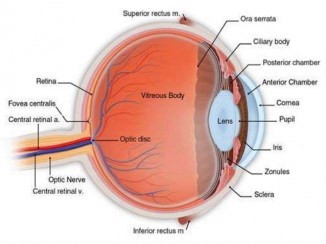

კატარაქტის განკურნების საიმედო საშუალებები!

კატარაქტა- თვალის ბროლის შემღვრევაა, იწვევს მხედველობის შესუსტებასა და დაკარგვას. საგნების კონტურები ბუნდოვანი, გაურკვეველი ხდება, თვალში თუ ვეღარ..